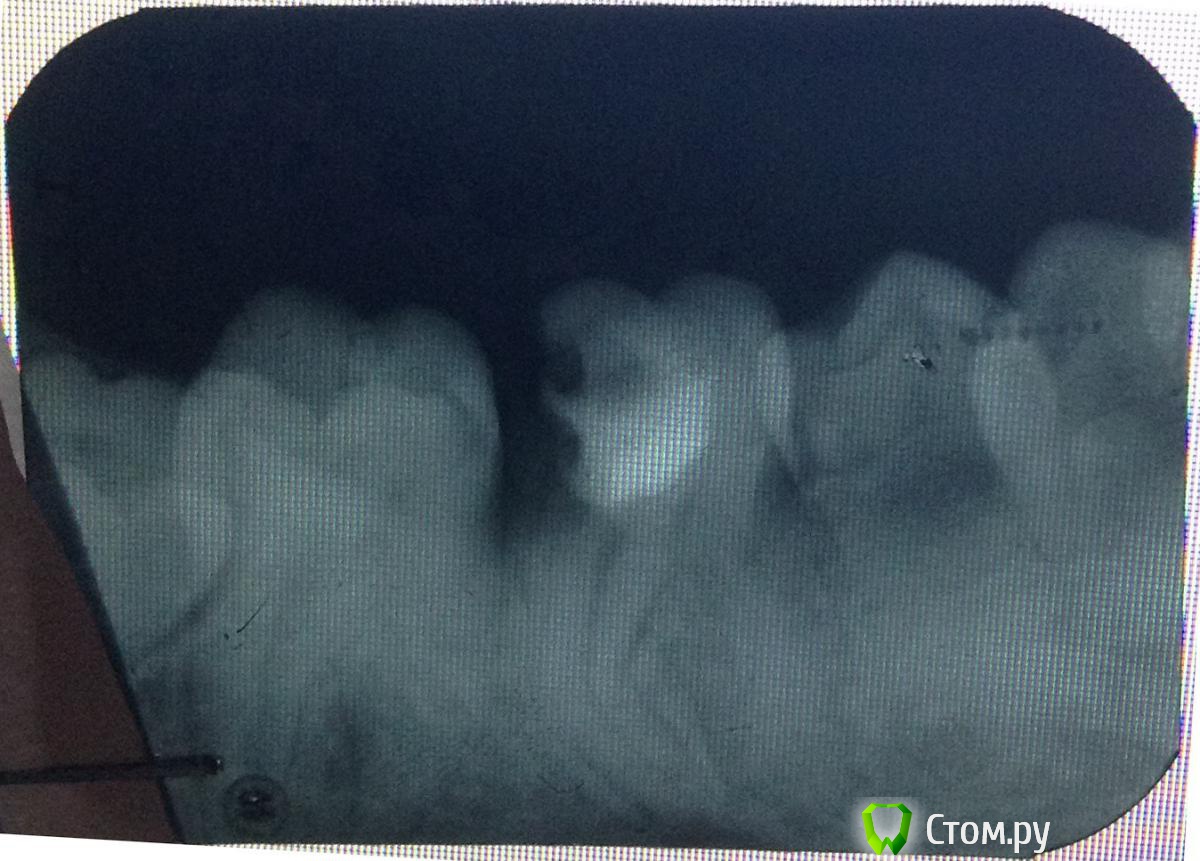

and13 Опубликовано 27 мая, 2014 Автор Поделиться Опубликовано 27 мая, 2014 Сделал фото на фоне монитора. Вроде получше видно. П.с. делают же вроде коронку на штифт, чтобы не удалять зуб? Или может что-то еще подскажите?Корни то целые? Ссылка на комментарий

Scrabble Опубликовано 27 мая, 2014 Поделиться Опубликовано 27 мая, 2014 (изменено) Кариес корня. Дёсны кровоточат-сходите к гигиенисту, почистите, соблюдайте рекомендации по гигиене полости рта. Вылечите все зубы, нуждающиеся в лечении. Имплантация всё равно будет не сразу после удаления. На восьмой зуб обратите внимание-его тоже лучше удалить(причина-он ретинирован и расположен под углом к корню седьмого. Сам никогда полностью не прорежется-и может повлиять на состояние седьмого) Изменено 27 мая, 2014 пользователем Scrabble Ссылка на комментарий

and13 Опубликовано 27 мая, 2014 Автор Поделиться Опубликовано 27 мая, 2014 (изменено) Не пойму, как же это только удалять. Медицина не шагнула еще настолько вперед, чтобы сохранить зуб? Мне просто не верится что нету альтернативного способа решения данной проблемыА почему 8ку удалить тоже надо? Совсем без зубов останусь, мне только 24 Изменено 27 мая, 2014 пользователем and13 Ссылка на комментарий

Scrabble Опубликовано 27 мая, 2014 Поделиться Опубликовано 27 мая, 2014 По поводу восьмого не переживайте-он всё равно не вырастет, только седьмой может с собой забрать. А шестой жалко, конечно. Но имплантация сейчас на высоте-надёжно будет и красиво. Ссылка на комментарий